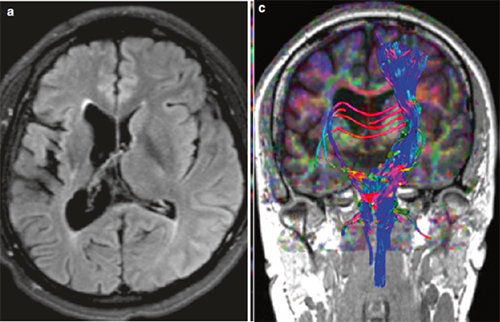

导致脑瘫的非进行性脑损伤病因,包括(1)发育不成熟的大脑(产前、产时或产后)、先天性发育缺陷(畸形、宫内感染) ;(2)获得性( 早产、低出生体重、窒息、缺氧缺血性脑病、核黄疸、外伤、感染);(3)脑瘫患儿出生时常常有早产或缺氧病史、以及感染、创伤等造成的脑损伤。常见的影像表现如下:

DTI显示右侧大脑联络纤维稀少(右侧大脑出血史)